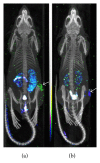

Molecular imaging is an emerging field that integrates advanced imaging technology with cellular and molecular biology. It can realize noninvasive and real time visualization, measurement of physiological or pathological process in the living organism at the cellular and molecular level, providing an effective method of information acquiring for diagnosis, therapy, and drug development and evaluating treatment of efficacy. Molecular imaging requires high resolution and high sensitive instruments and specific imaging agents that link the imaging signal with molecular event. Recently, the application of new emerging chemical technology and nanotechnology has stimulated the development of imaging agents. Nanoparticles modified with small molecule, peptide, antibody, and aptamer have been extensively applied for preclinical studies. Therapeutic drug or gene is incorporated into nanoparticles to construct multifunctional imaging agents which allow for theranostic applications. In this review, we will discuss the characteristics of molecular imaging, the novel imaging agent including targeted imaging agent and multifunctional imaging agent, as well as cite some examples of their application in molecular imaging and therapy.